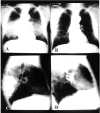

Fig. (6)

Chest radiograph of a patient with the chronic form of paracoccidioidomycosis, in antero-psterior and laterak view, showing bilateral and symmetrical alveolar lesions before (A and C) and after (B and D) treatment.